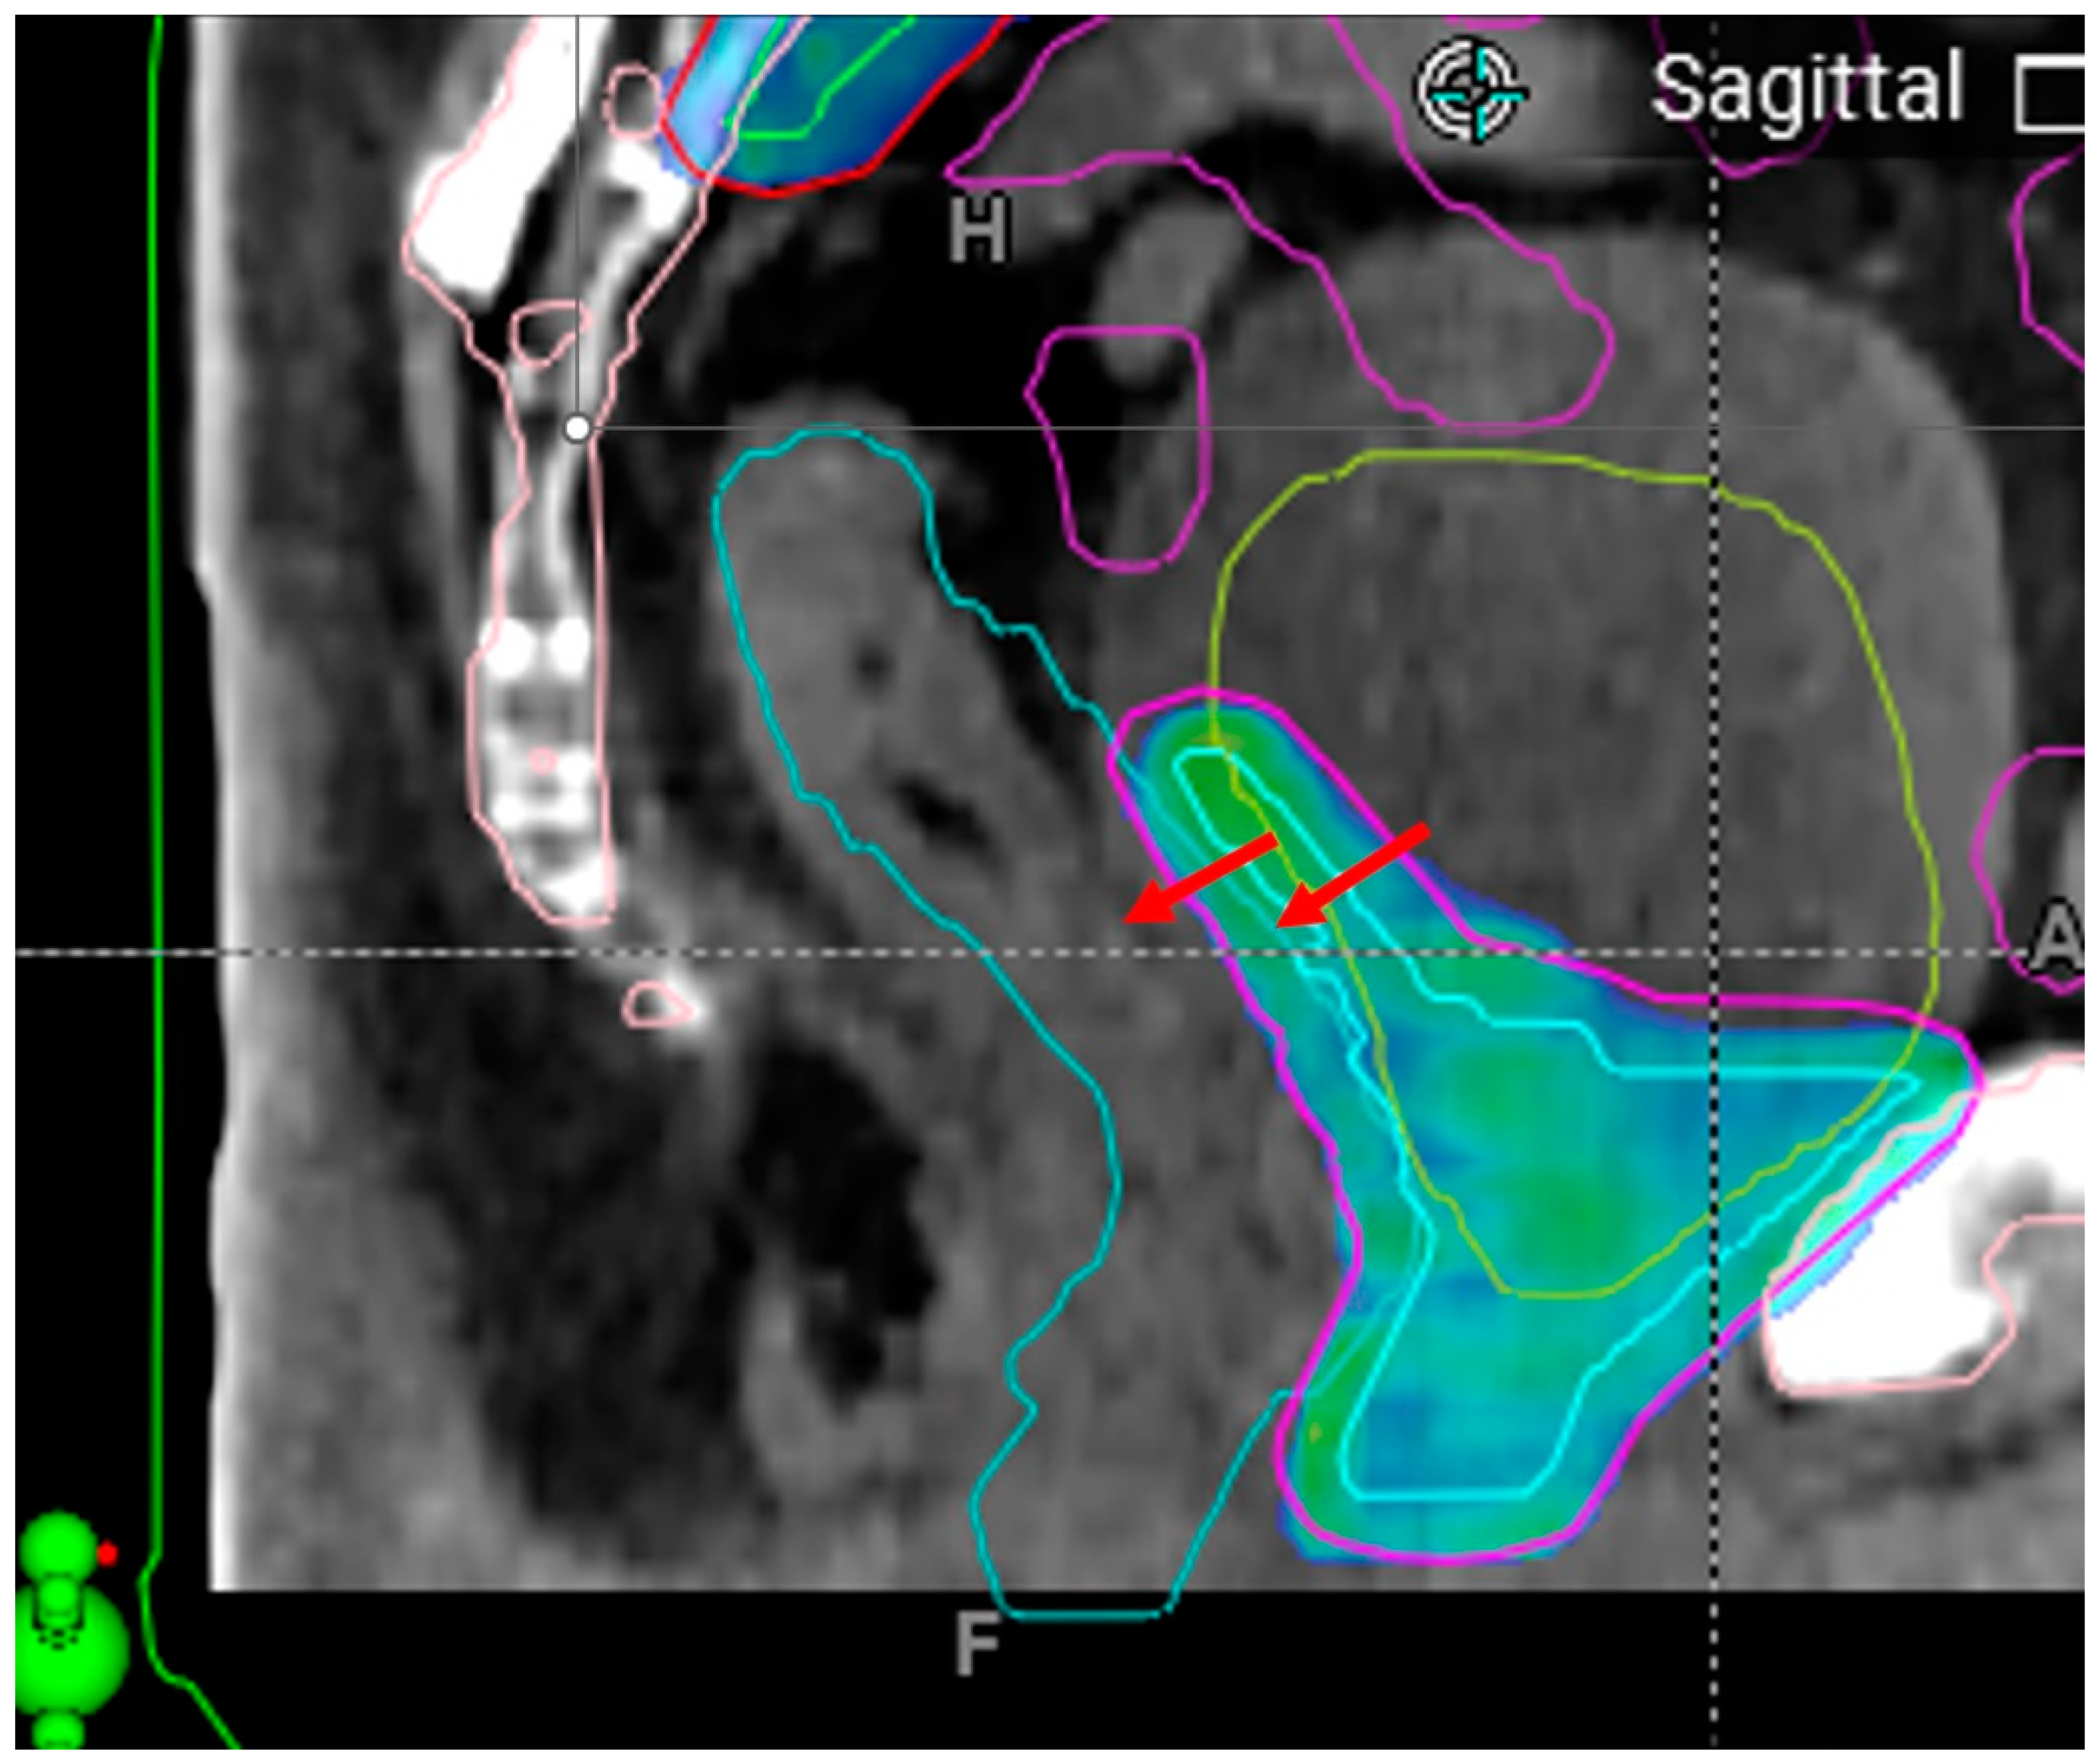

3.2.2. Patient-Driven Challenges

3.2.3. Treatment Planning and Execution Failures